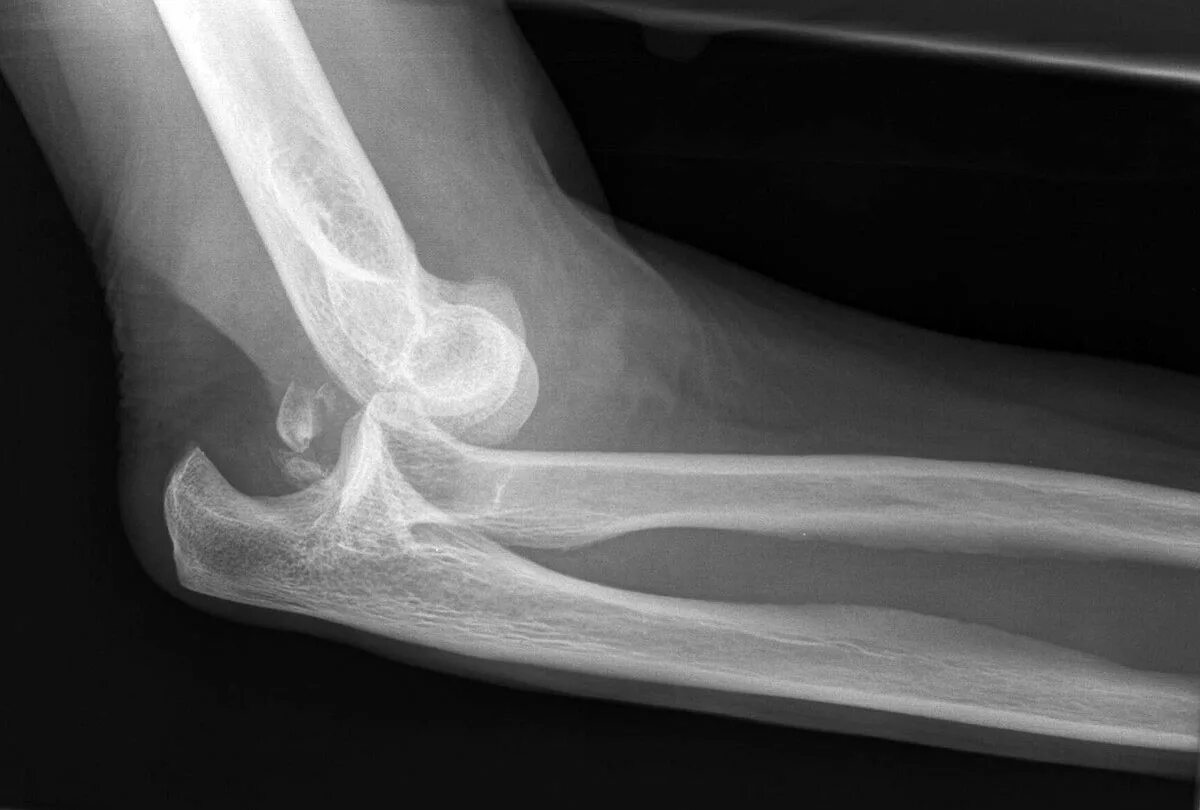

Задний вывих локтевого сустава.

Вывих локтевого сустава рентген. задний вывих локтевого сустава рентген. подвывих локтевого сустава. подвывих локтевого сустава рентген.

Вывих костей предплечья рентген. вывих локтевого сустава рентген. передний вывих локтевого сустава рентген. задний вывих локтевого сустава рентген.